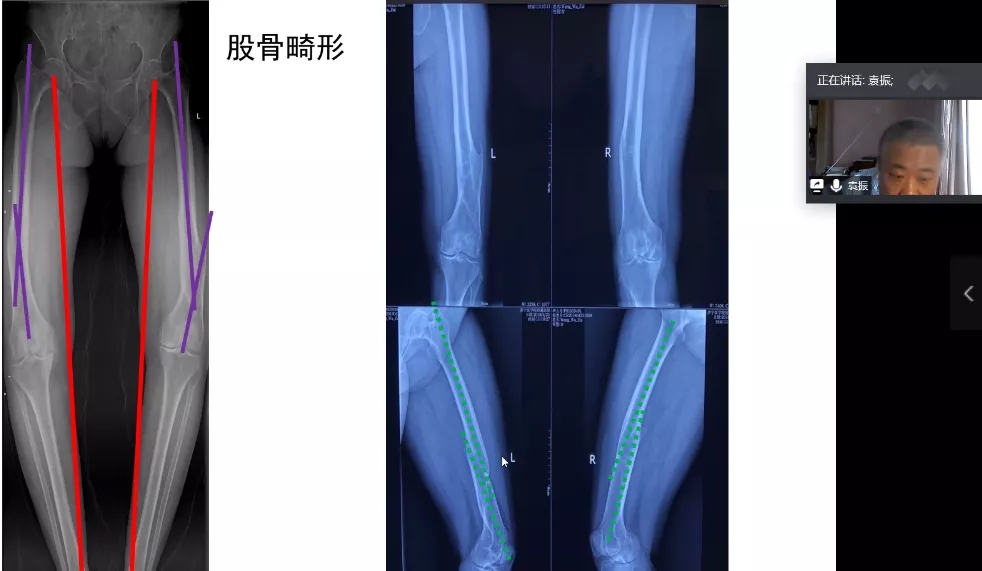

孙教授强调,正确的对线对假体安装和术后舒适度十分关键,行TKA之后髋关节旋转中心、膝关节旋转中心、踝关节旋转中心,三者在正位和侧位一定在一条线上。股骨及胫骨截骨垂直于机械轴,可完成正确对线。在进行膝外翻TKA时,通常伴随髋外翻,此时应为患者照全长片,准确测量膝关节外翻角度,若只照膝关节正位片,则很容易导致错误测量股骨解剖轴和股骨力线,对手术造成影响。此外,孙永强教授用模型直观的演示了在进行截骨时若患者股骨远端有前弓,该如何决定髓内定位杆的进针点。

膝关节畸形是临床上TKA中最常见症状,占TKA患者症状中的80%之多。软骨磨损、边缘骨赘增生、髁间窝增生等都可能引起后方关节囊和内侧结构挛缩,外侧结构松弛,造成膝内翻畸形。此外,胫骨畸形、股骨畸形、混合畸形同样会引起骨型畸形造成膝内翻。

袁振教授向大家介绍如何通过参考各种角度,来判断患者内外翻畸形。